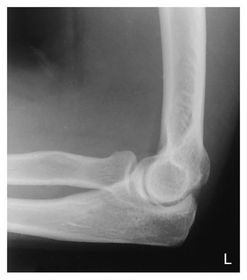

a. outer ridges of capitulum and trochlea b. trochlear notch c. trochlear sulcus

1. trochlear sulcus 2. outer ridges of capitulum and trochlea 3. trochlear notch

AP Lateral Elbow 60-75 kVp 40 SID 10x12 IR nongrid CR @ midelbow joint MUST SEE 3 concentric arcs, olecranon process